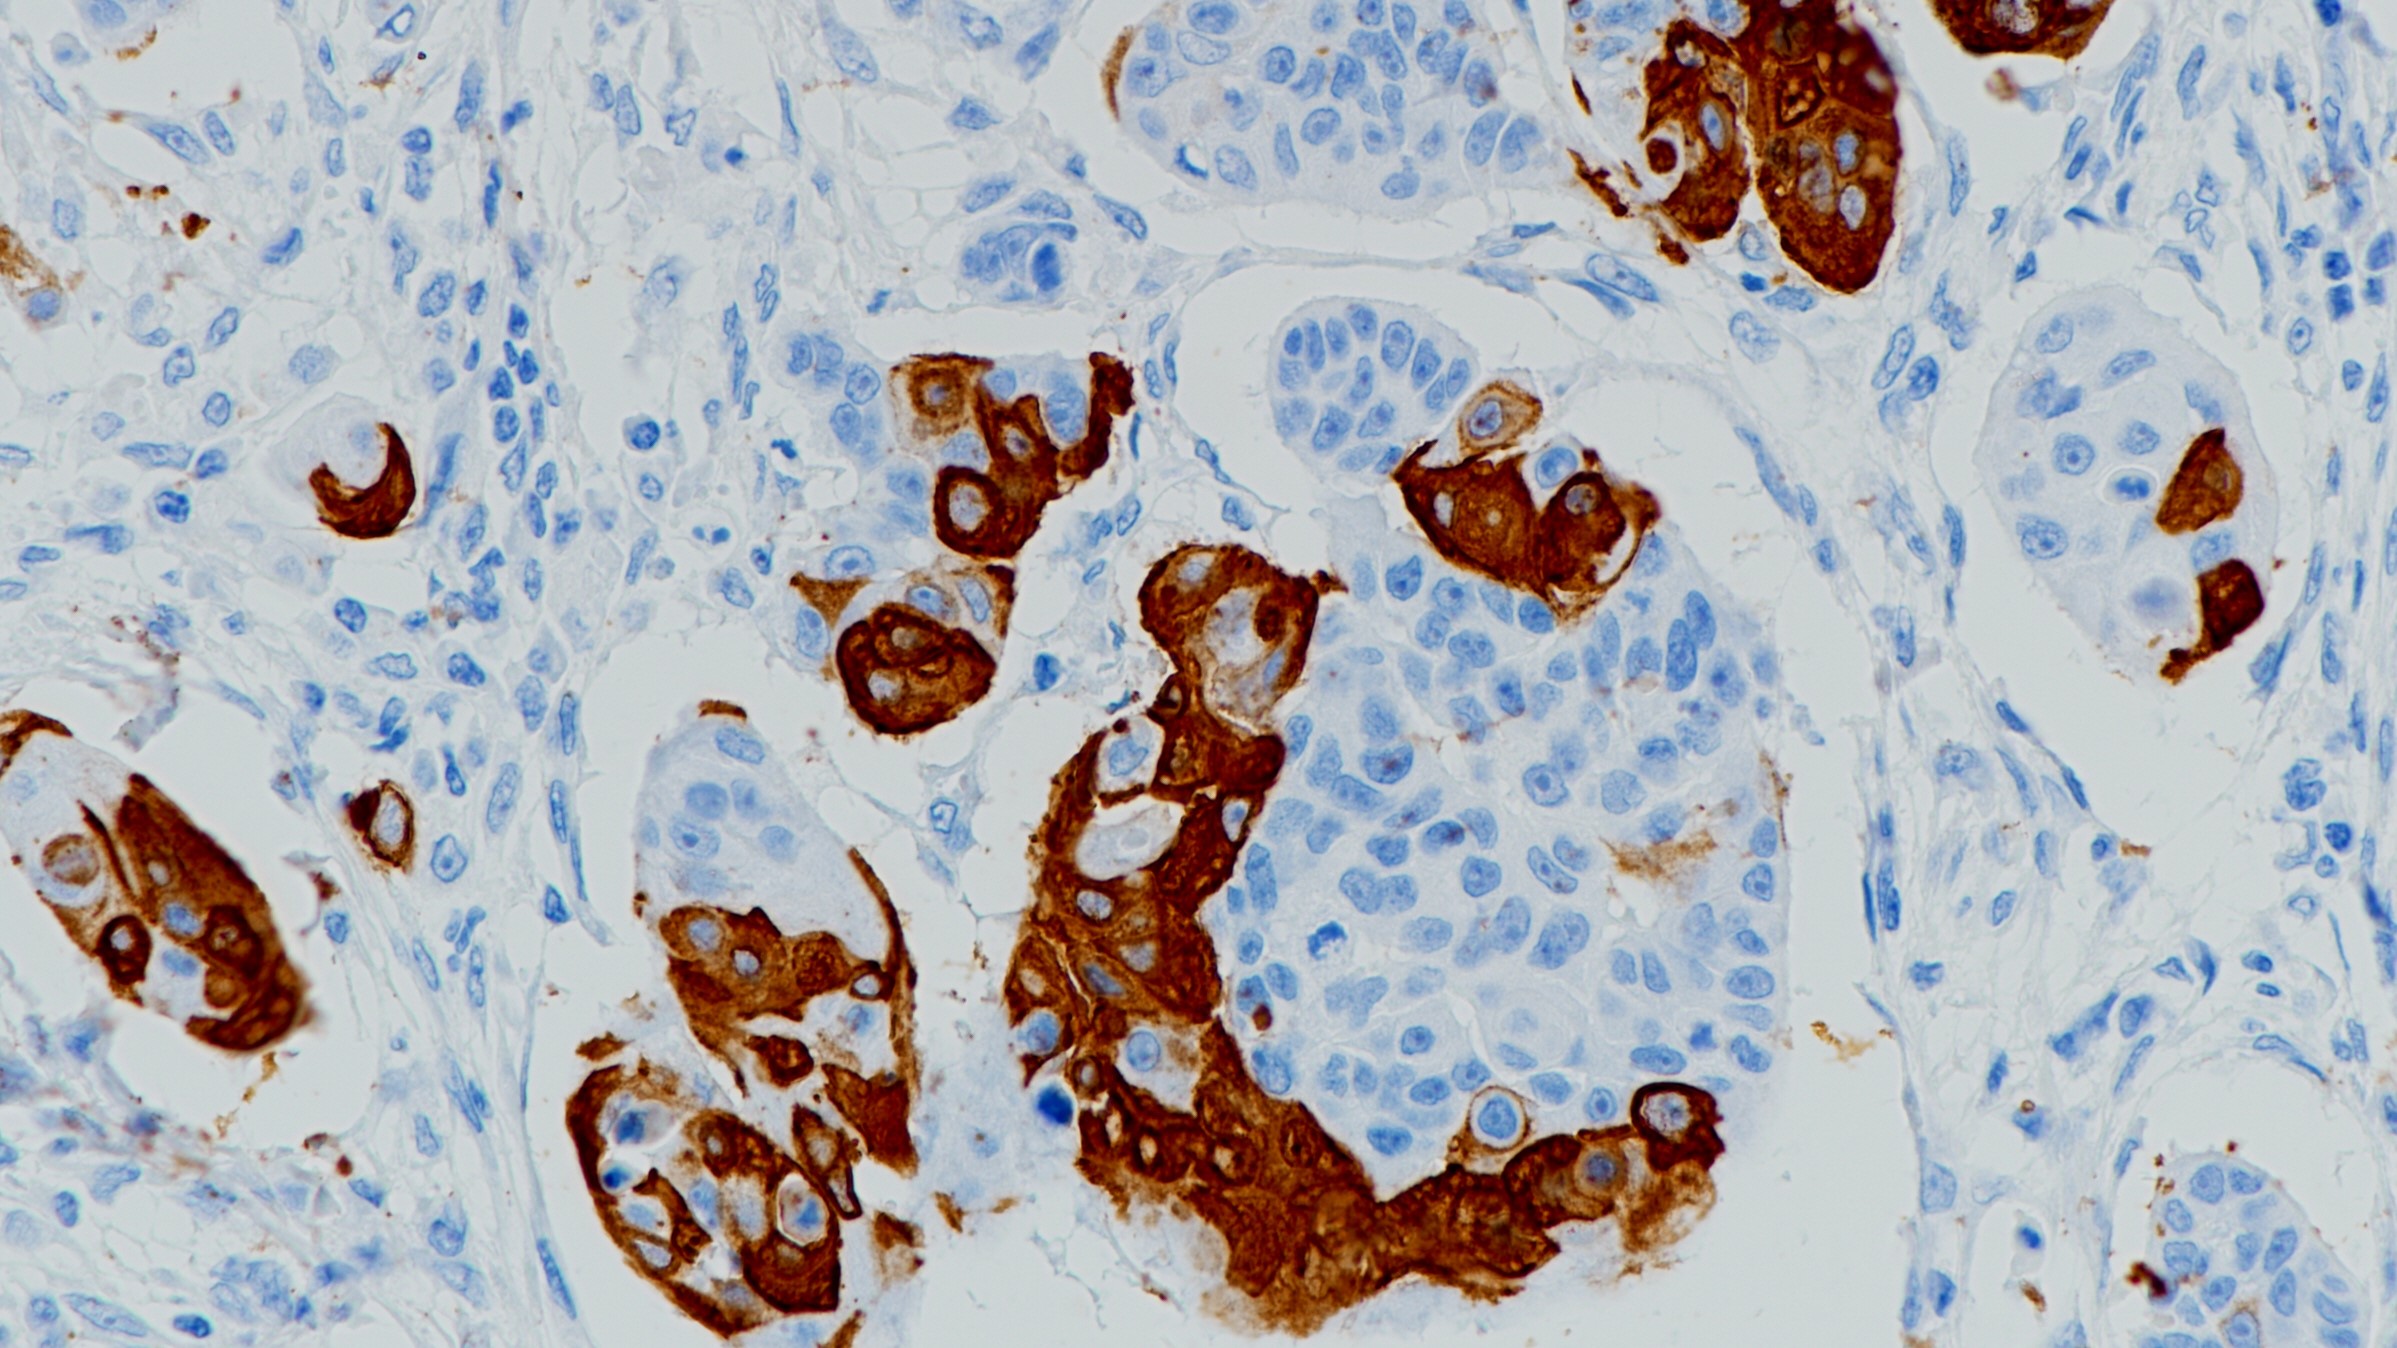

1.马静,王凯靖,柴佳,赵丹珲,范林妮,杨重飞,刘一雄.转移性肾细胞癌组织中β-catenin表达与临床病理特征及预后的关系[J].山东医药,2020,60(14):64-66